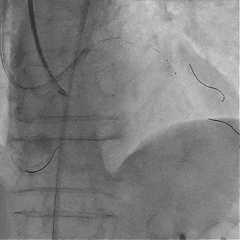

对角支送入IVUS导管,在IVUS实时指引下用尝试穿刺闭塞段

导丝未能进入闭塞段,导丝进入间隔支

逆向造影指引下继续尝试穿刺闭塞段

导丝远端与逆向造影不重叠,未在血管真腔

反复调整导丝最终进入D2#,可见导丝远端与D2侧枝重叠,证明远端位于真腔

微导管交换工作导丝至D2#远端